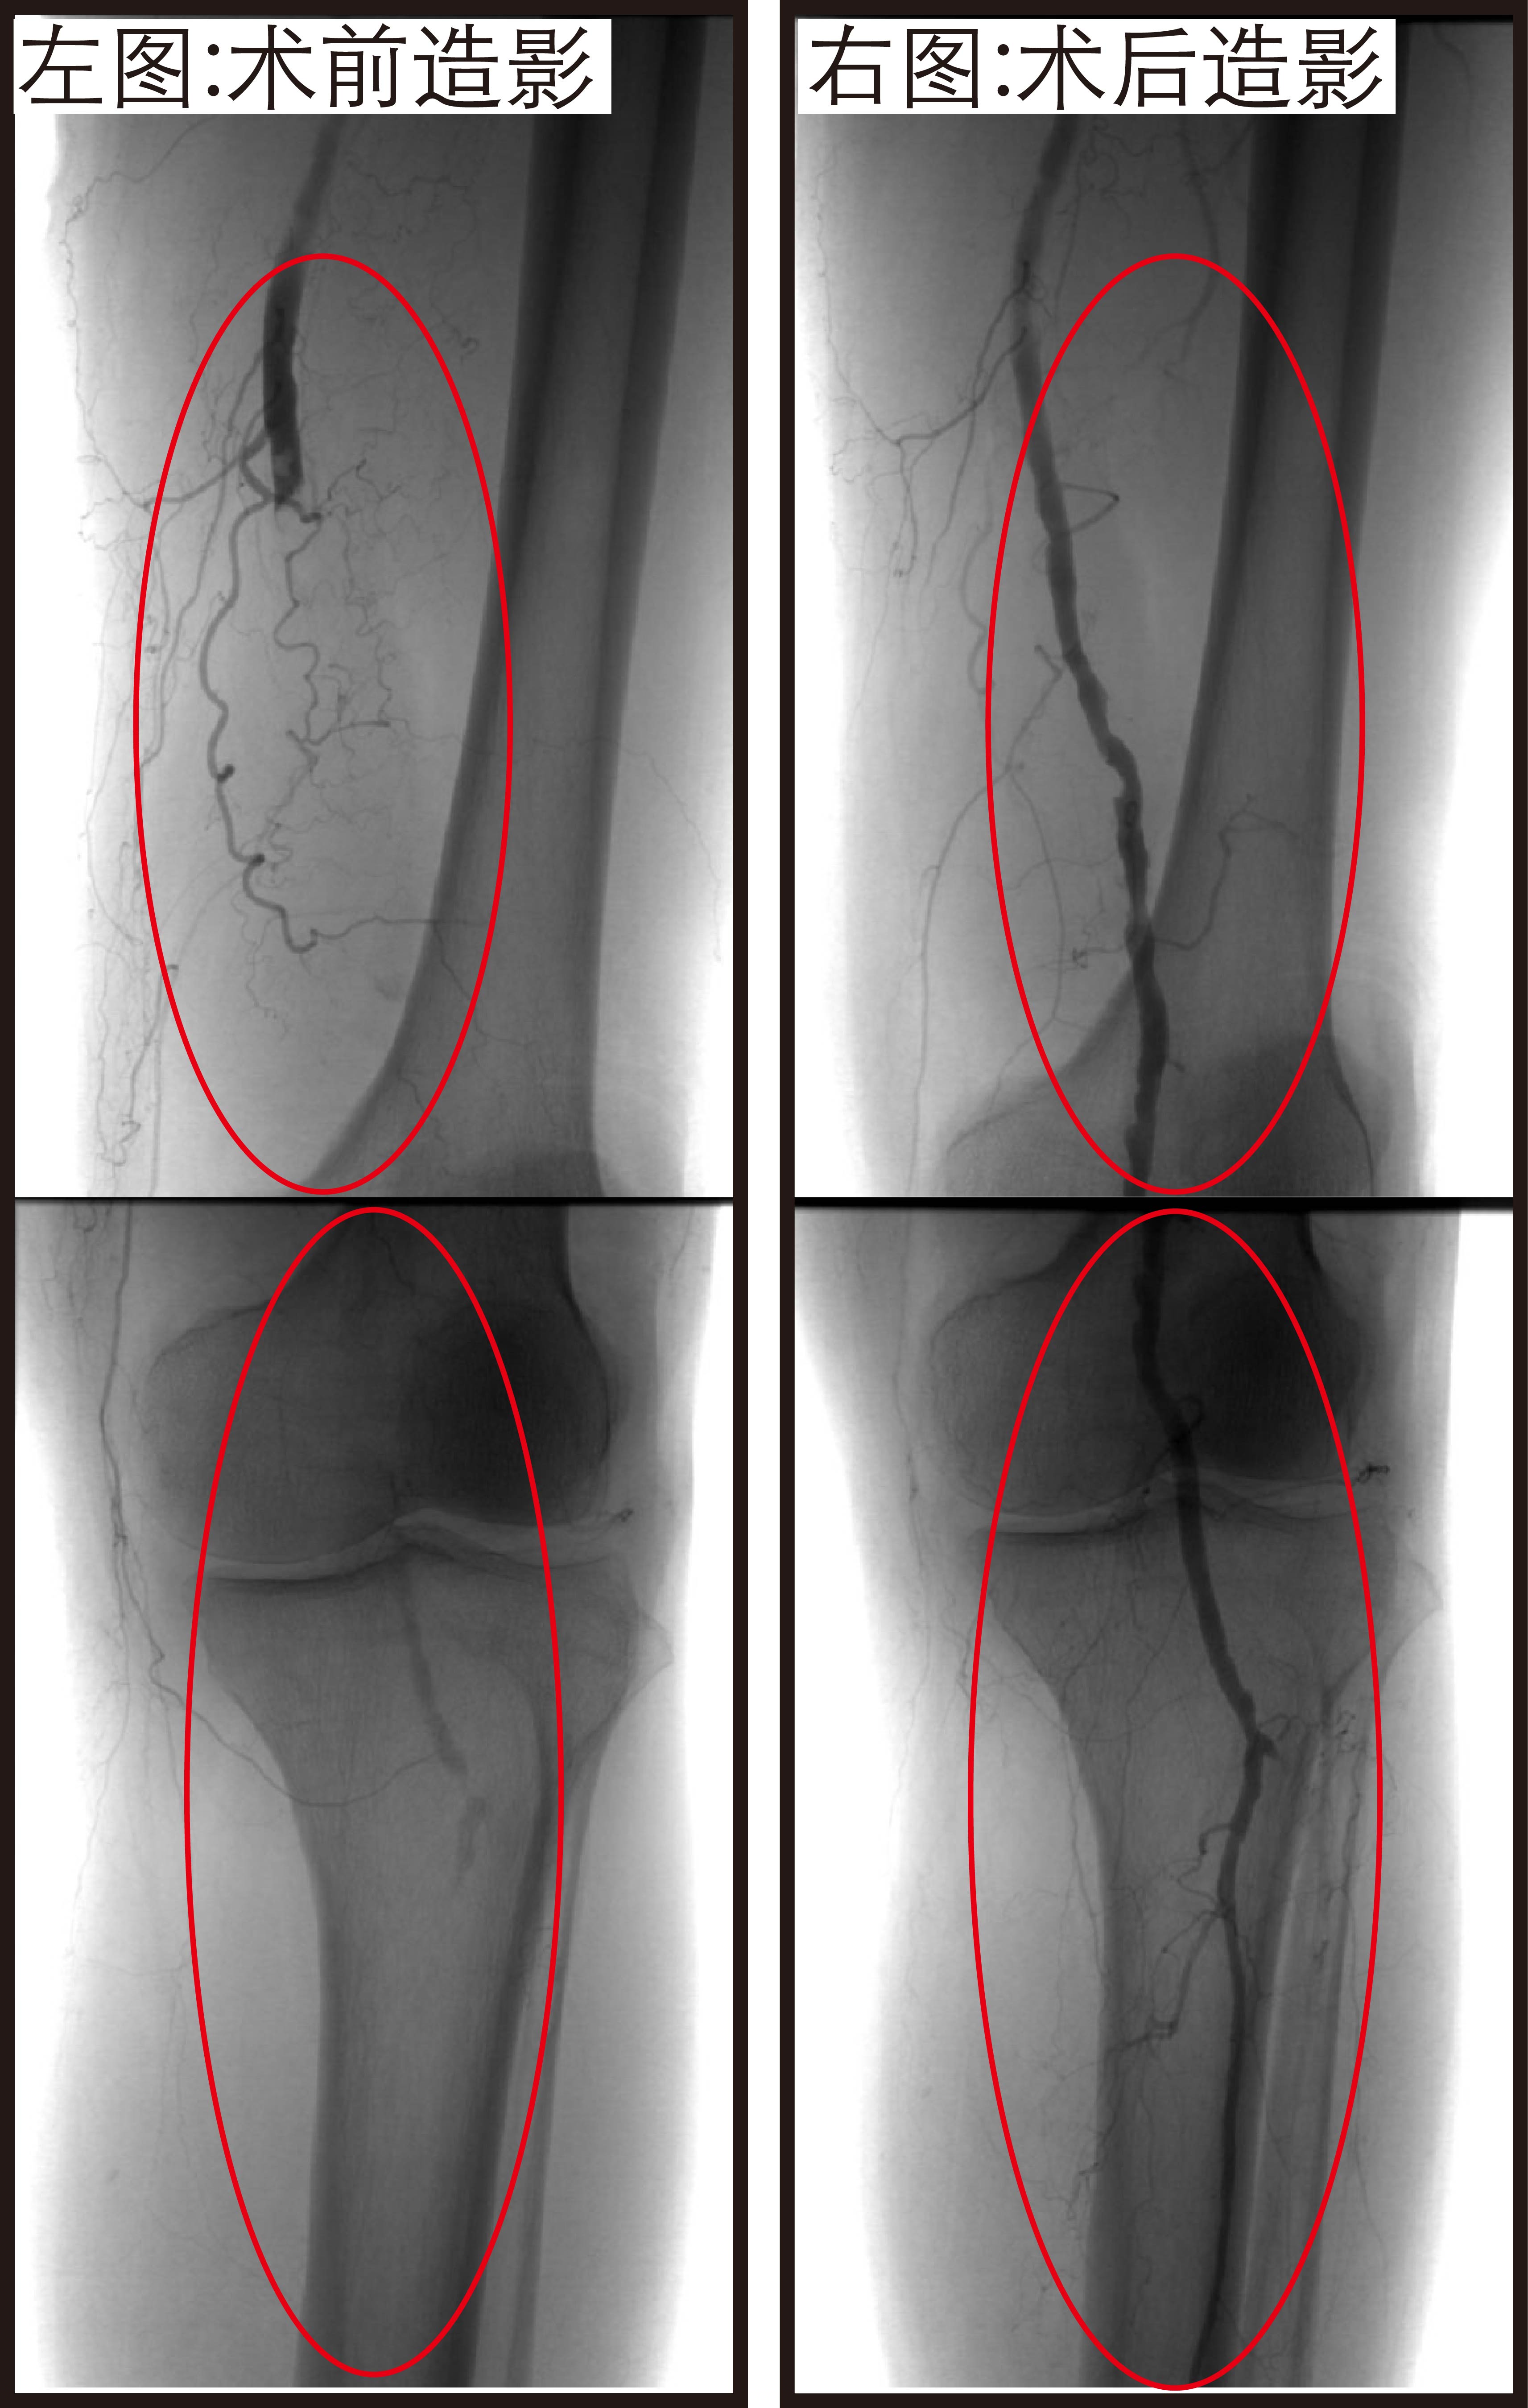

手术在局麻下进行,邓宏平教授团队在老人腹股沟处选择 1 毫米左右股动脉穿刺点,穿刺成功后引入机械吸栓导管,「定点」吸出血栓,精准疏通闭塞的血管。经过不到一个小时的微创手术,闭塞的血管被成功开通,下肢动脉血液供应完全恢复。术后老人左腿的疼痛麻木症状消失,皮温很快恢复正常。

手术 6 小时后老人就下床活动了,术后第三天复查下肢动脉通畅,顺利出院。